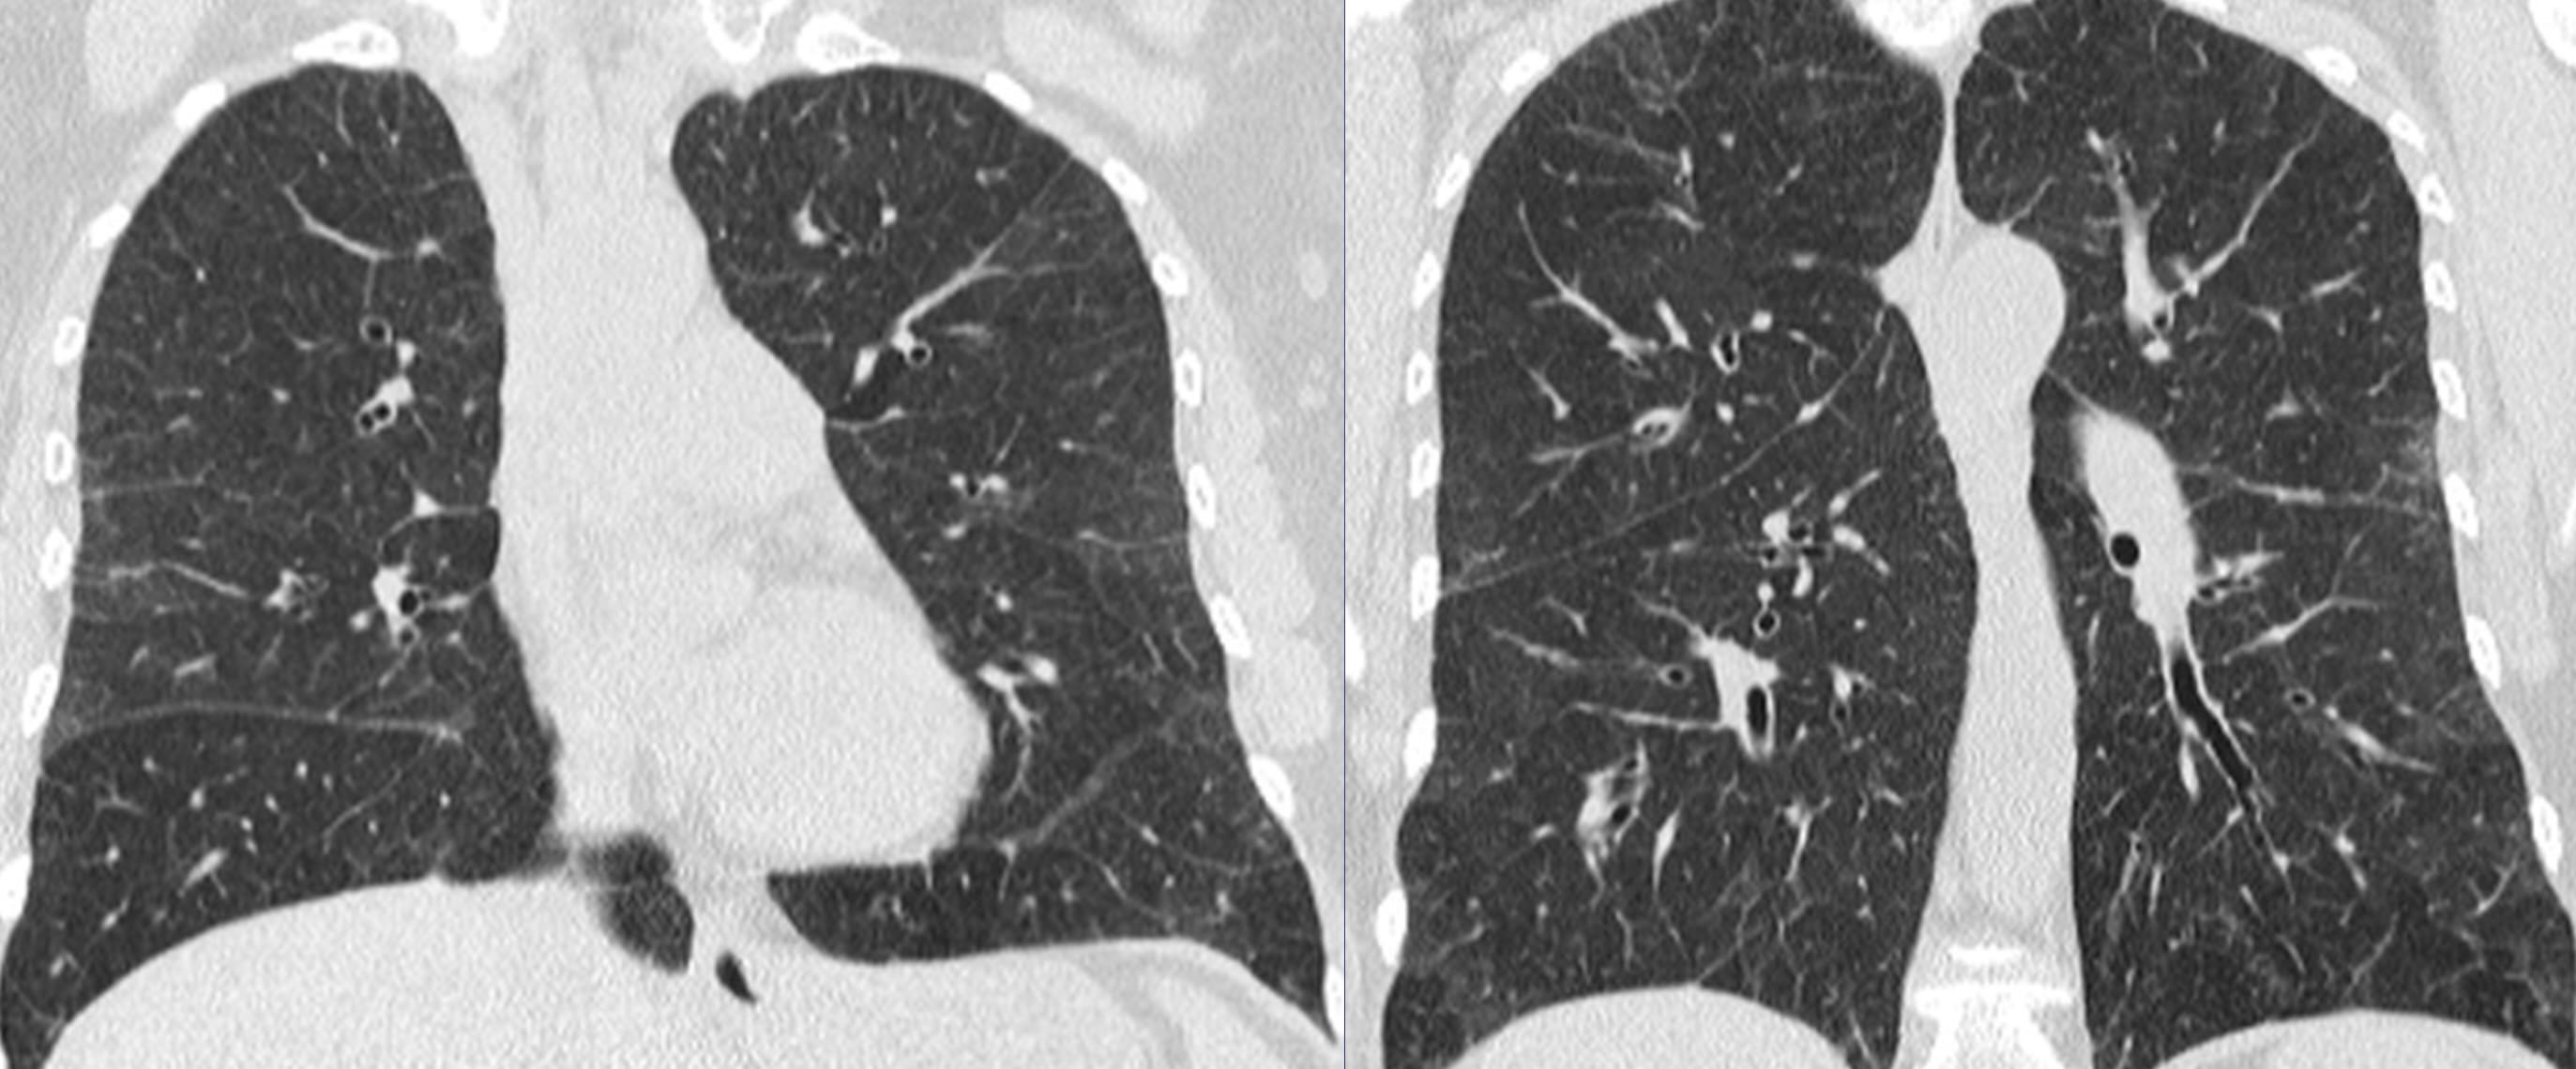

Unexplained, new dyspnea in a healthy female

- lymphatic obstruction, typically by metastatic tumor–lymphangitic tumor spread–manifests as lung edema

- the edema is typically interstitial, may be focal and asymmetric, and associated with transudative pleural effusions

- lymphangitic tumor spread may be accompanied by other forms of metastases, such as solid nodules

- uncommonly, lymphangitic tumor spread is the first manifestation of cancer